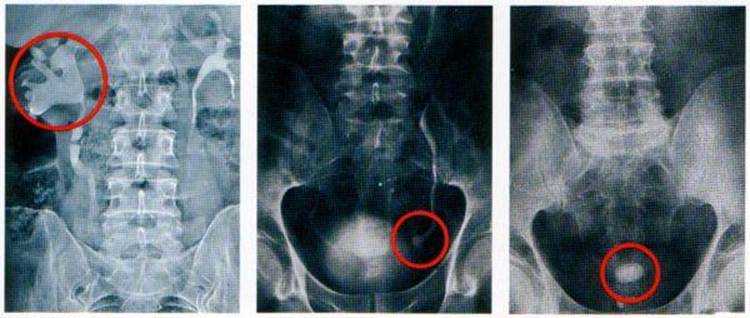

Мочекаменной болезни подвержены люди любого возраста и пола. Диагностируется при помощи медицинских клинических анализов и общих жалоб пациента. Для заболевания характерно образование камней в мочевыделительной системе. Они могут быть разными по величине и диаметру, чаще всего встречается песок. Бывают и образования размерами от 0,5 см до 5—6 см.

Уролитиаз – патология обмена веществ, характеризуется образованием конкрементов в любом участке мочевыводящих путей. Заболеванию в равной мере подвержены представители обоих полов старше 30 лет. При подозрении на мочекаменную болезнь, анализ мочи является первым звеном диагностики. Результат исследования дает представление о химическом составе образований, наличии вторичного воспалительного процесса.

Человек может годами носить в почке камни и даже не подозревать этого. Клинические проявления возникают при начале движения конкремента и при перекрытии им мочевыводящих протоков. Основной симптом – сильнейшая боль – почечная колика, изменяется количество мочеиспусканий и качества урины. Какие жалобы предъявляют пациенты:

- Дизурический синдром. При обструкции конкрементами возникают трудности с выведением жидкости, суточное количество мочеиспусканий уменьшается. Движение камней в нижней части мочеточника, напротив, вызывает частое непреодолимое желание помочиться.

- Изменяется внешний вид урины. Чаще всего пугает появление крови, моча приобретает розовый цвет из-за того, что острые шипы камней травмируют слизистую. Другая жалоба – обнаружение мутного осадка. Хлопья в моче могут быть заметны невооруженным взглядом. Такое состояние сопровождается тупой болью в пояснице или внизу живота, субфебрильной температурой.

- Изменение кислотности. В норме pH урины нейтральна – 7,0. При окислении (показателях выше 7,0) возникает подозрение на образование уратов. Ощелачивание способствует развитию фосфатов, в их пользу говорят и обнаруженные крупные хлопья в моче. Слабокислая среда показательна для оксалатов.

- Микрогематурия – показатели эритроцитов, превышающие 1 – 3 в п/зр., различается только под микроскопом. Макрогематурия заметна невооруженным глазом.

- Белок в моче появляется при сочетании мочекаменной патологии с воспалительным процессом.

- Повышенное содержание солей время от времени встречается у каждого человека, связано это с дефицитом потребления жидкости. Регулярный солевой осадок свидетельствует о развитии патологии. Обнаружение кристаллов струвитных камней говорит об инфекционной природе МКБ. Часто в дополнение определяют бактериурию и протеинурию.